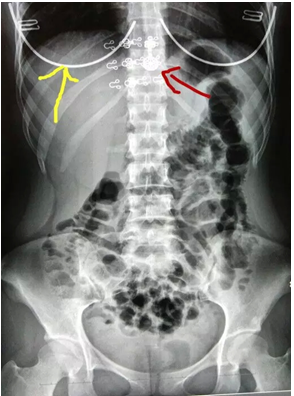

图3

再看看图三,这是一个立位腹部平片,用老百姓的话就是拍肚子的X光片子。那么肚子部分的有金属的东西都必须拿掉(比如裤子的裤链,扣子,外面裤子就需要往下脱了),但是拍肚子的时候要包括部分的下胸部,我们可以看到片子上黄色箭头指的是胸罩的钢圈,红色箭头指的就是后面的扣子。这个时候扣子就跟胸椎重叠了,如果这个骨头有事,有可能就看不出来了,就是导致了漏诊。